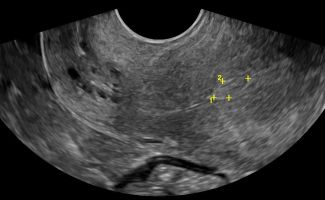

- Ωοθήκες: Η απεικόνιση των ωοθηκών περιλαμβάνει την αξιολόγηση του μεγέθους, της μορφολογίας και της υφής τους. Με το Διακολπικό Υπερηχογράφημα, μπορούν να μετρηθούν τα ωοθυλάκια και να διερευνηθεί η παρουσία συνδρόμου πολυκυστικών ωοθηκών. Οι εστιακές βλάβες στις ωοθήκες, συμπαγείς ή κυστικές, μπορούν να αξιολογηθούν ως καλοήθεις ή ύποπτες, με τη βοήθεια του Έγχρωμου Doppler για την απεικόνιση της αγγείωσης και της ροής του αίματος.